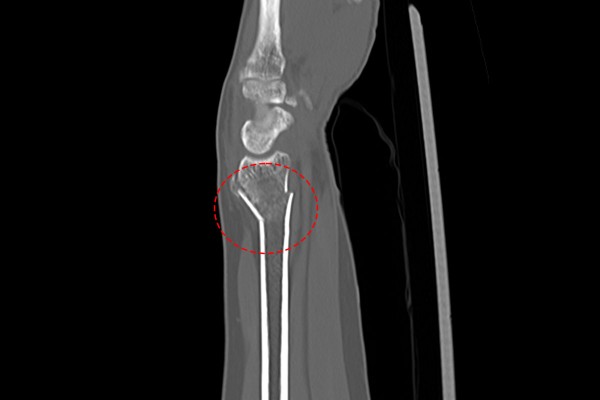

CT 검사 결과를 확인해보니, 손목이 골절되어 뒤로 꺾여있는 것이 확인되어 손목 원위요골 골절(Fx. distal radius wrist Rt.)을 진단하였습니다.